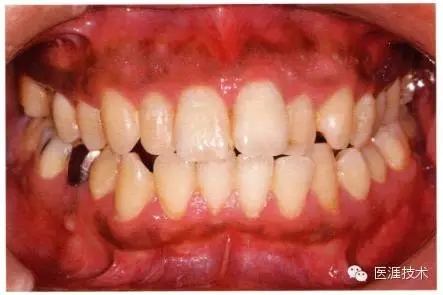

26歲男性牙齦炎的臨床圖像

26歲男性。開口呼吸?;旌嫌醒例l發(fā)紅、腫脹與纖維性肥厚。菌斑干燥牢牢黏住,刷牙難以刷掉。